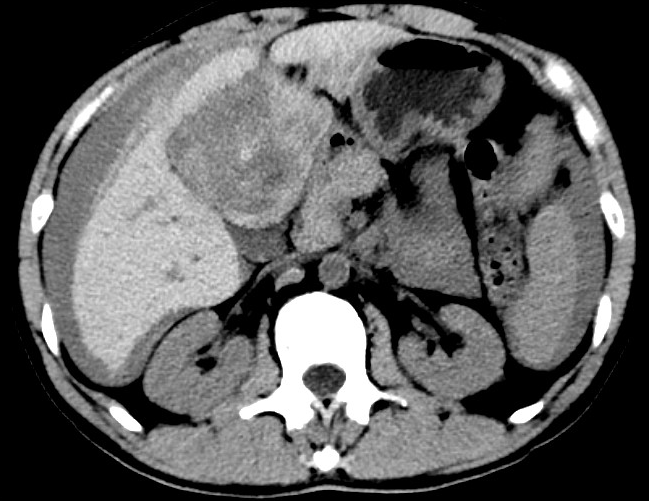

放下電話的白葦急赴消內(nèi)三搶救室會診,經(jīng)仔細(xì)查體、對患者腹部CT進(jìn)行詳細(xì)閱片、綜合評估患者后,考慮患者是肝占位破裂出血?;颊卟∏槭志o急、一刻也不容耽誤,需立刻急診行肝動脈造影 栓塞術(shù)進(jìn)行止血治療,在與患者家屬溝通后,立即通知消化介入室準(zhǔn)備急診手術(shù)。

入手術(shù)室時(shí),患者神志迷糊,口唇干燥、重度貧血貌,心電監(jiān)護(hù)提示:心率140-160次/分,血壓70/43mmHg,這是失血性休克的表現(xiàn)!白葦快速建立靜脈通道緊急給予輸血,升壓,止血等液,立即給予肝動脈造影,術(shù)中發(fā)現(xiàn)肝左葉疑似腫瘤病灶、病灶周圍血管分支有造影劑外溢,考慮血管破裂出血,迅速給予栓塞微球進(jìn)行肝動脈栓塞。整個(gè)手術(shù)過程不足20分鐘,術(shù)后即刻患者心率降至100-110次/分、血壓升至90/60mmHg。

術(shù)后給予積極抗炎,止血,保肝、利尿等對癥治療,復(fù)查血常規(guī)提示活動性出血停止后,在超聲引導(dǎo)下行腹腔穿刺引流術(shù),術(shù)后3天共引流出血性腹水約4000ml?;颊呓?jīng)復(fù)查各項(xiàng)指標(biāo)均趨于正常,復(fù)查CT提示腹腔積血已基本吸收,患者康復(fù)出院。